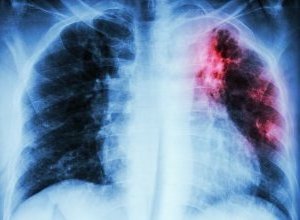

An ingestible sensor that enables health workers to check that patients have taken their medication could revolutionise tuberculosis treatment, particularly in developing countries, The Daily Telegraph reports researchers believe.

New ways to ensure TB patients comply with their treatment are desperately needed. The report says patients with the most straightforward form of the deadly infectious disease have to take a cocktail of drugs over a six-month period – and if they fail to stick to the regime, they risk the disease returning in a drug-resistant form.